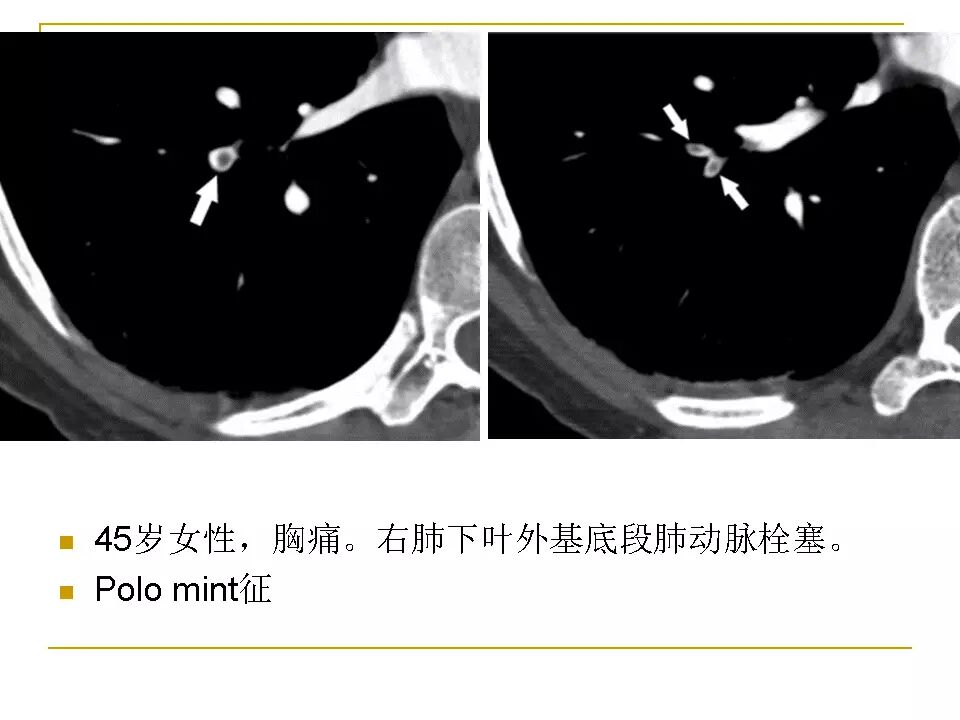

【RadioGraphics】肺动脉栓塞CTA